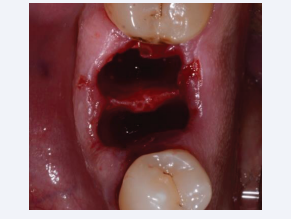

Two to three days prior to surgery, each patient was provided a professional tooth cleaning for plaque and calculus removal and prescribed a 0.20% chlorhexidine rinse three times a day for 14 days. Patients began a five-day course of amoxicillin (1 gram tablets, twice daily) starting 12 hours before surgery. Local anesthesia consisting of articaine with adrenaline (1:100.000) was induced in the vestibular and lingual area. Each tooth was extracted atraumatically using a flapless technique to preserve the blood supply of the alveolar bone plates. An odontotomy was created with a diamond burr to separate the roots and elevators were used to luxate each root that were extracted one at the time while taking care to preserve the interradicular septum and the alveolar walls. An alveolar curette was used to thoroughly debride the alveolus after tooth extraction.

The rational for not using any bone graft was to eliminate the confounding factor and to have a better standardization of the protocol among the different clinical cases (Figure 1).

Occlusal view of flapless fresh extraction site showing interradicular  septum preservation.

Figure 1: Occlusal view of flapless fresh extraction site showing interradicular septum preservation.